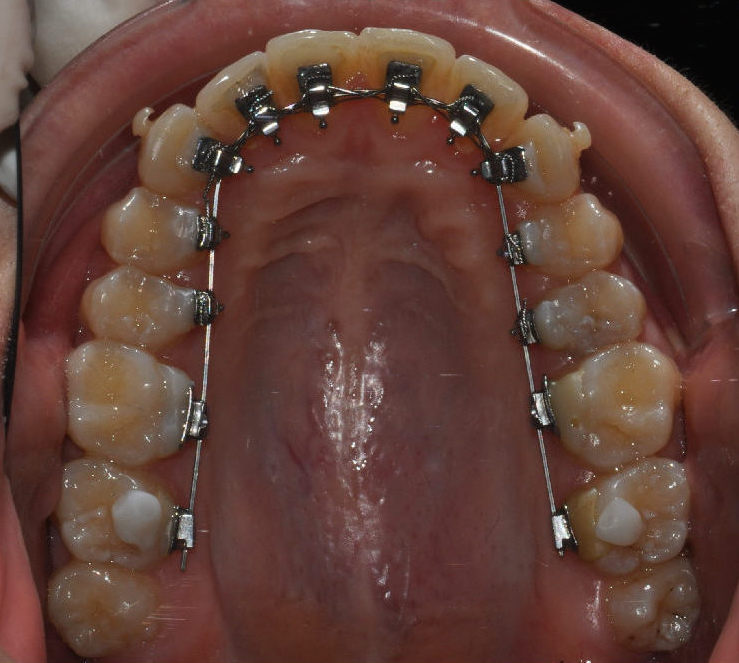

Ortodonzia invisibile: Quando le disarmonie del sorriso possono essere gestite spostando i denti e ci sono le condizioni cliniche per farlo, si possono anche impiegare apparecchiature molto poco visibili, o quasi invisibili.

Si tratta delle mascherine ortodontiche trasparenti o dell’apparecchiatura linguale.

Nel caso della terapia linguale, invece, l’apparecchio viene posizionato sulla superficie interna dei denti.

Anche in questa metodica si sfrutta la tecnologia digitale: gli attacchi, che compongono l’apparecchiatura, vengono prima collocati su modelli virtuali 3D e poi trasferiti sulla dentatura del paziente.